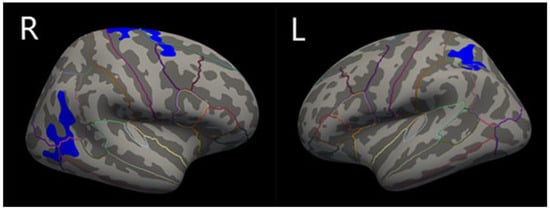

3.2. Cortical Thickness

| L_superior parietal (mm2) | 2.294 ± 0.082 | 2.120 ± 0.092 | 0.000 * |

| R_inferior parietal (mm2) | 2.570 ± 0.107 | 2.357 ± 0.114 | 0.000 * |

| R_superior frontal (mm2) | 2.627 ± 0.142 | 2.389 ± 0.229 | 0.000 * |